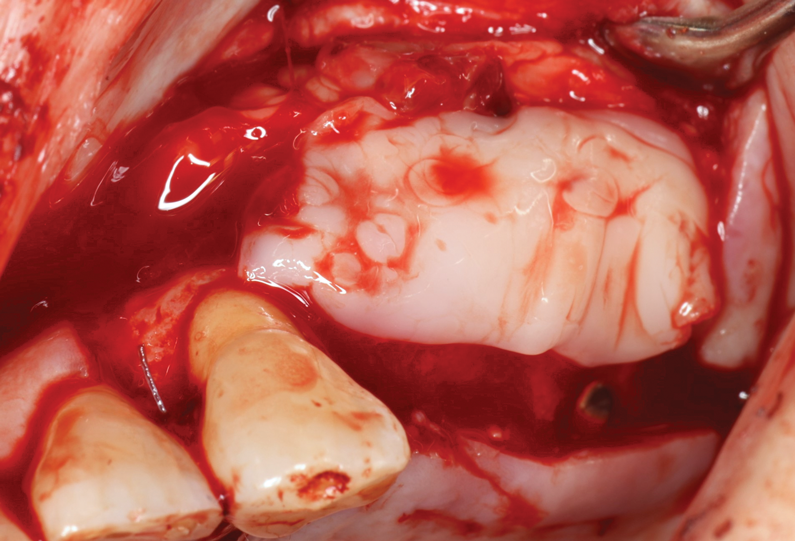

Fig 5. Bone replacement graft placement within prepared sinus site.

Figure 5